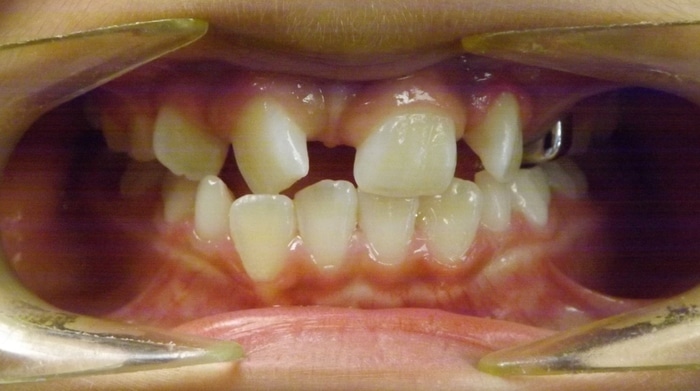

Christopher was a Phase I case that presented with a Class III bite on the right side and around a 90 degree rotation of his upper right central and lateral incisors. During Phase I we placed upper 2×4 brackets (brackets on upper 4 front permanent teeth) since he still had several primary teeth left. We began Phase II and at this time Christopher had 5 mm of upper crowding and 3 mm of lower crowding. We placed brackets on the upper and lower arches and had him wear elastics during treatment. Christopher ended with a really beautiful Class I bite and smile.